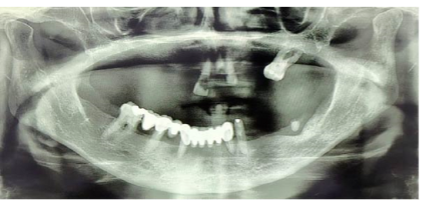

- Immediate postoperative radiograph confirmed accurate implant positioning

- Radiographic evaluation showed stable implant positioning